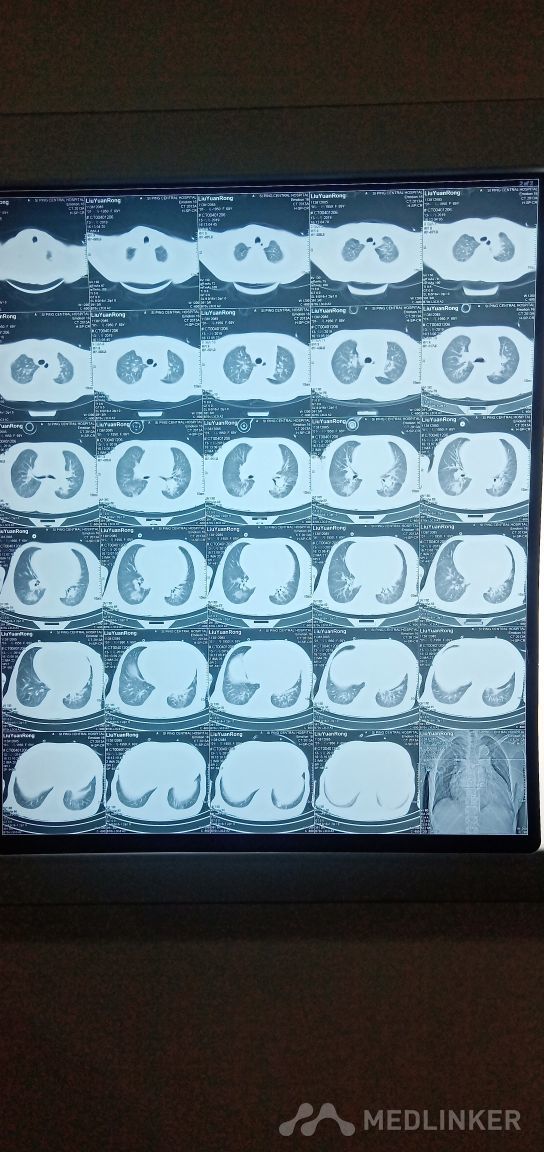

慢性心衰,周身浮肿。心脏不能承受之大。

患者间断胸闷气短十余年,加重伴烦躁不安,周身不适1周。肺底部少量湿罗音,1周未进食,烦躁不安, BNP >35000.表述不清疼痛部位。拒绝检查和治疗。